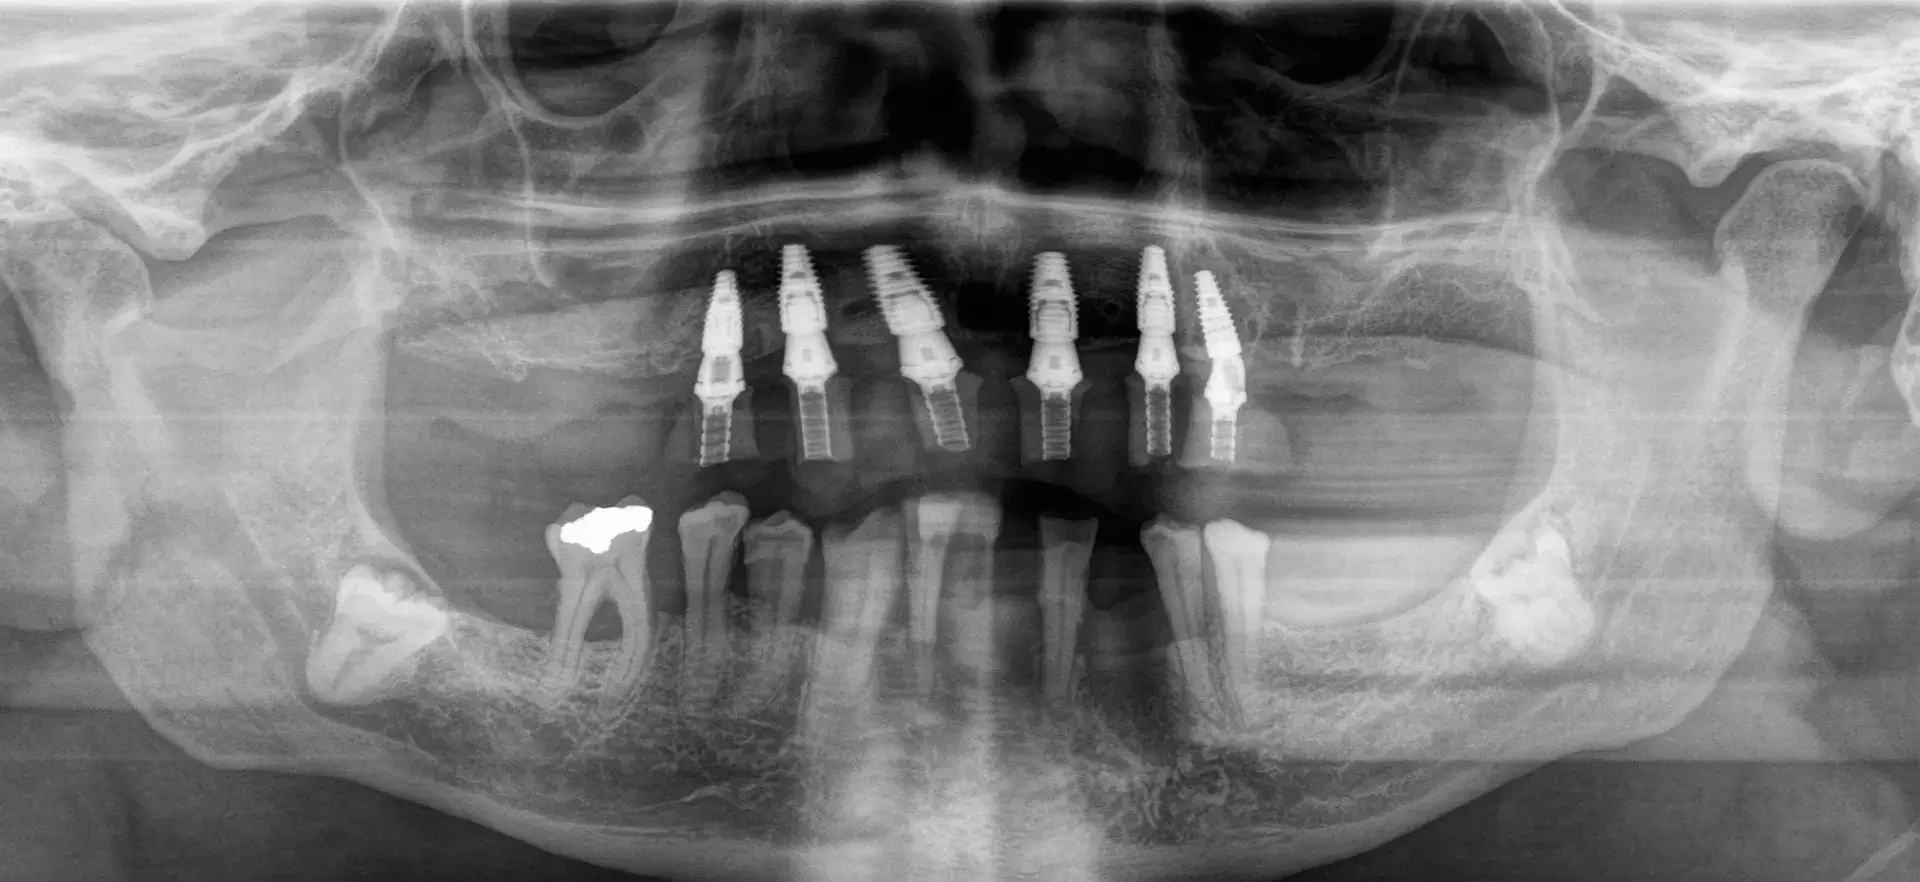

Das Prinzip ist so simpel wie genial: Sechs strategisch platzierte Implantate pro Kiefer bilden das Fundament für eine festsitzende, voll belastbare Zahnreihe. Der entscheidende Vorteil für Sie: Durch die präzise Ausnutzung des vorhandenen Kieferknochens können wir in vielen Fällen auf einen langwierigen Knochenaufbau verzichten.

Sie erhalten noch am Tag der Implantation einen provisorischen, festsitzenden Zahnersatz. Das bedeutet: Keine wackelnden Prothesen mehr. Sie verlassen unsere Praxis mit einem Gefühl, als wären es Ihre eigenen Zähne.